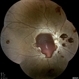

- anaemic retinopathy

- Scanning laser ophthalmoscope

- COLOUR FUNDUS PHOTOGRAPH OF A 24 YEAR OLD FEMALE WITH ANAEMIC RETINOPATHY AND MACULAR EDEMA